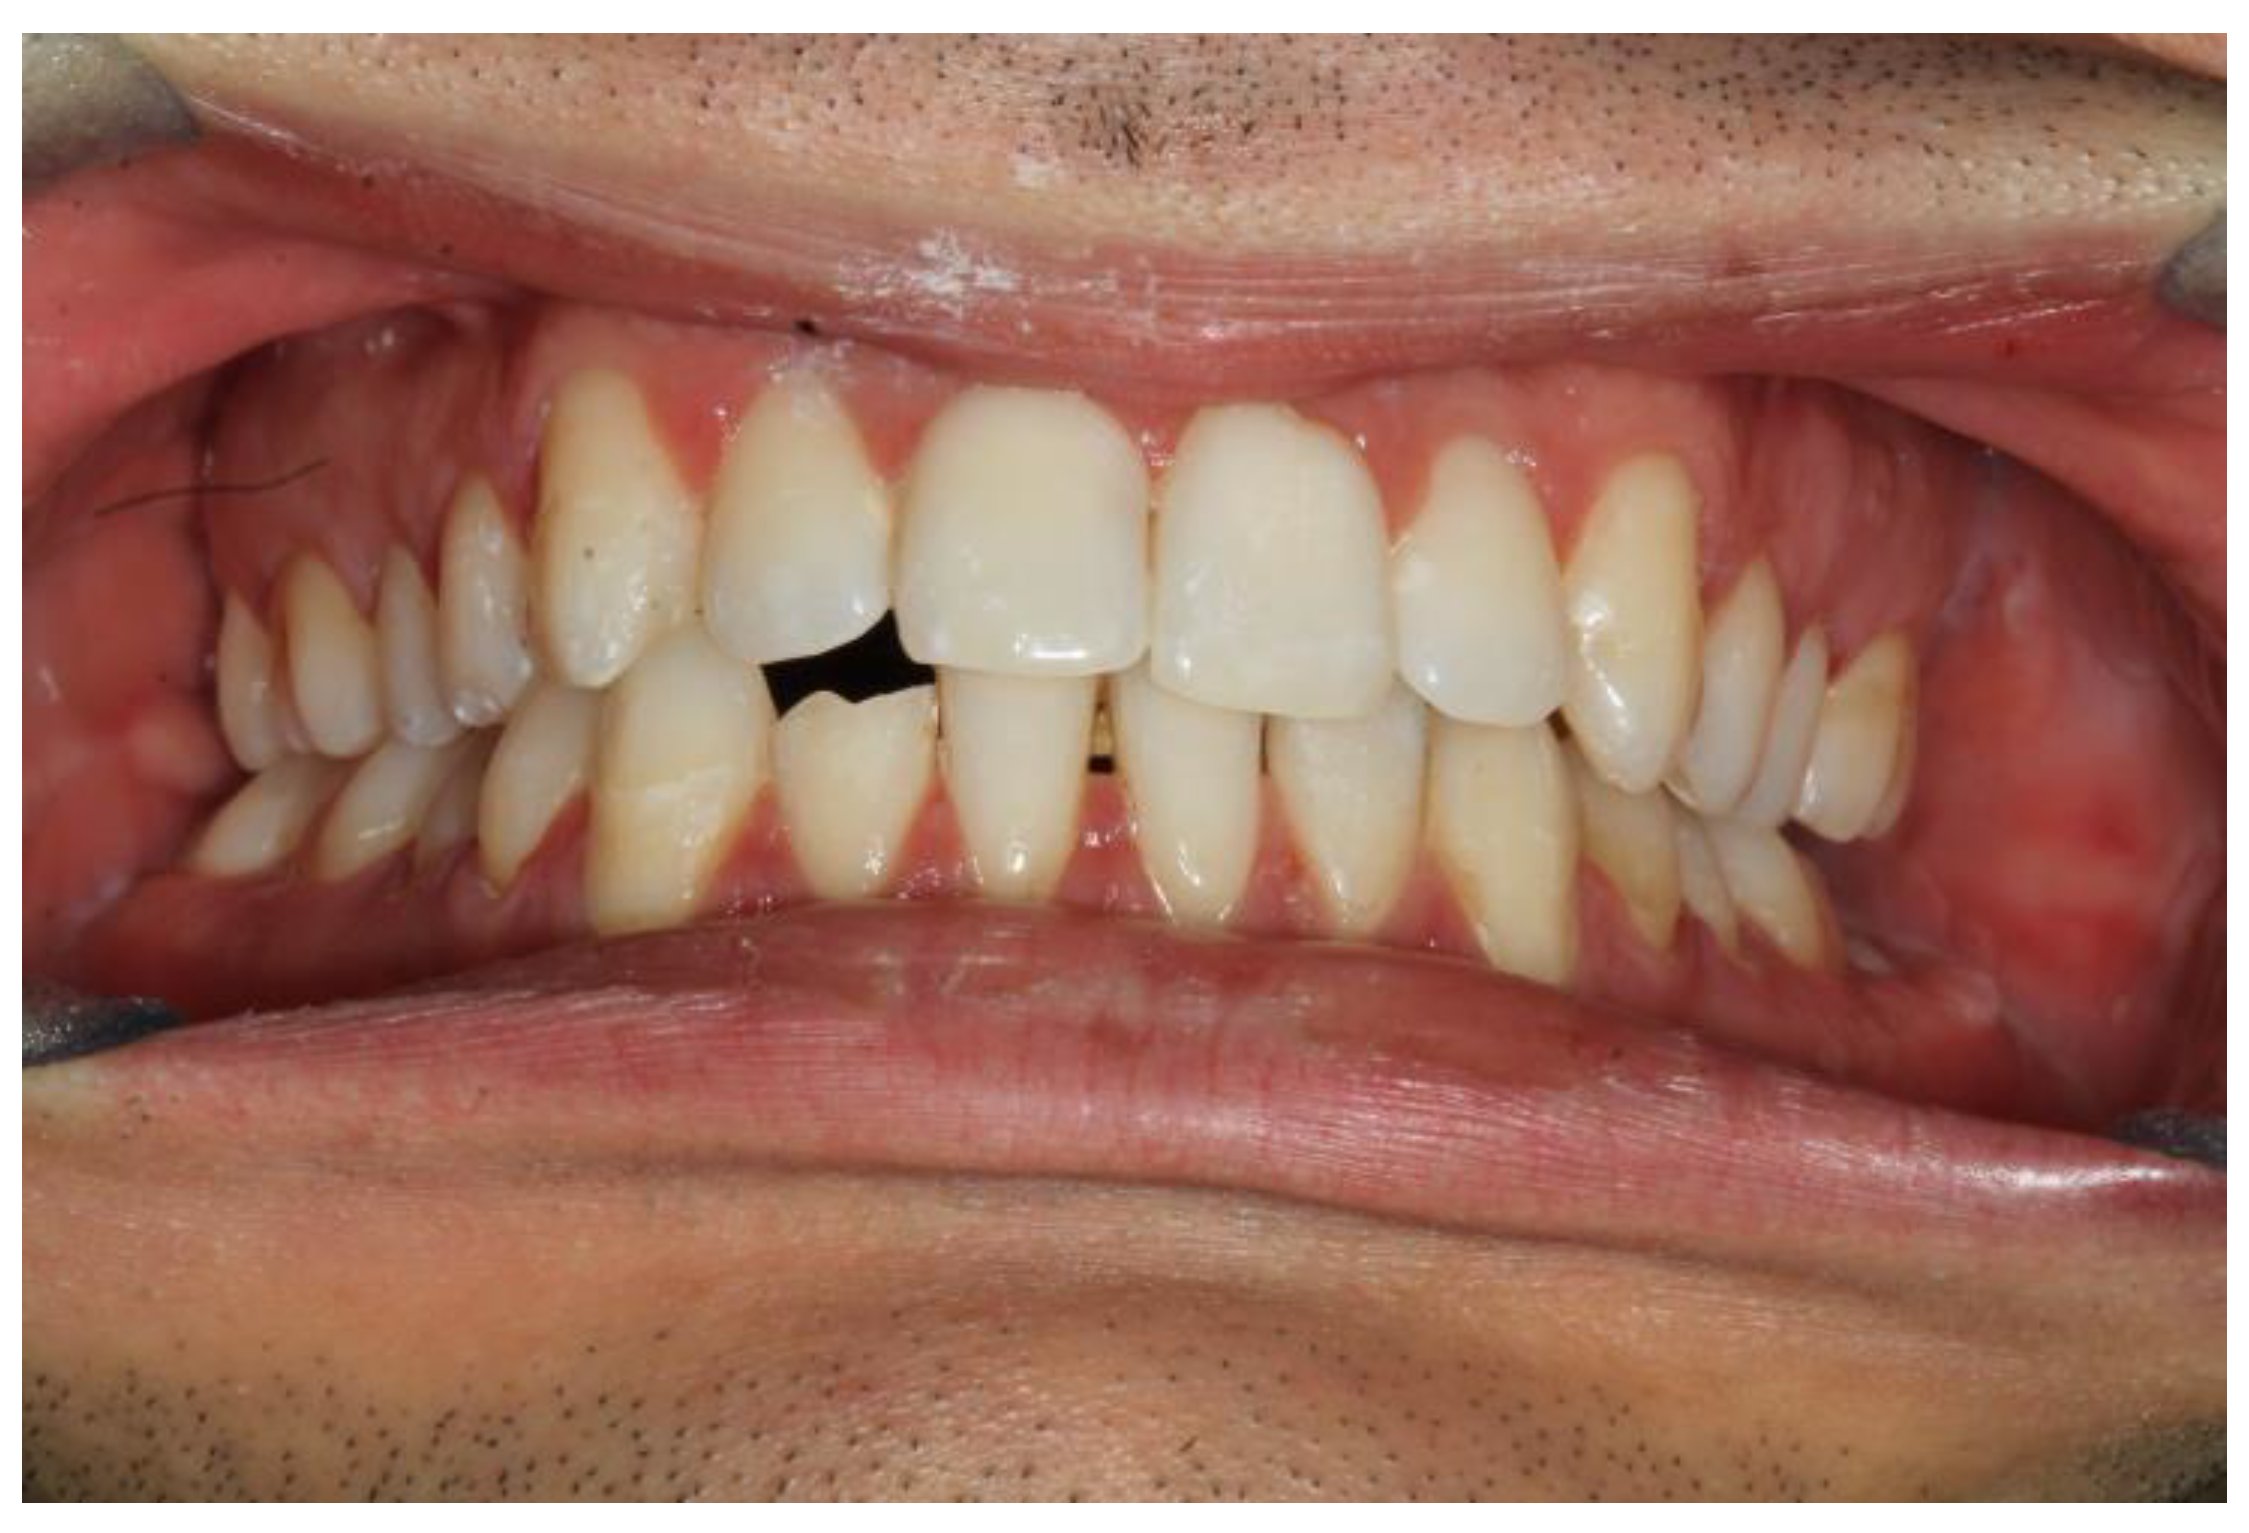

The first patient was a woman with a right sub-condylar non-displaced fracture, with sound permanent dentition, and without comorbidities (Figure 3). She had already received orthodontic treatment for agenesis of the upper lateral incisors, with space closure by means of mesialization of the upper teeth. She had a molar class II, the upper canines in the place of lateral incisors, and a deep bite. In this case, the application of a fixed orthodontic appliance would have implied the need to be absolutely passive in order not to compromise the result of the orthodontic therapy. Furthermore, the anterior deep bite would have been an impediment for the correct positioning of the brackets on the lower incisors.

Figure 3. Patient 1 with a right sub-condylar non-displaced fracture, with sound permanent dentition and without comorbidities.